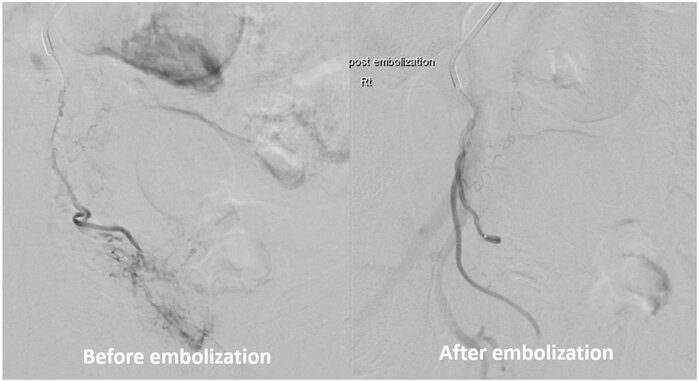

For patients with recurrent hematuria or at high risk of bleeding (e.g. on anti-coagulants), treatment options such as GreenLight laser vaporization and prostatic artery embolization may be considered. GreenLight laser has the property of vaporizing the prostate tissue and controlling bleeding at the same time. Prostatic artery embolization works by occluding the blood supply to the prostate gland, hence reducing bleeding and causing shrinkage of the prostate tissue. Apart from good hemostatic effects, both procedures are able to improve lower urinary tract symptoms at the same time.

Prostatic Artery Embolization